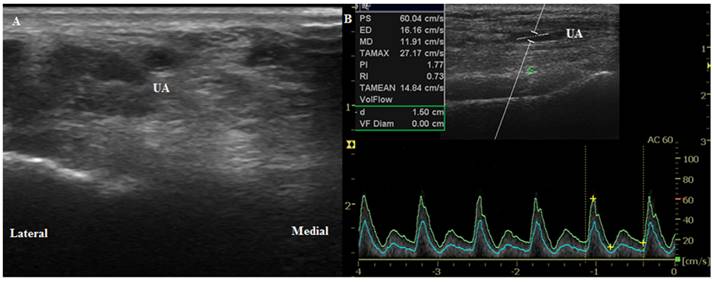

The wrist joint of each patient was extended up to 45° on a wrist board as described in a study by Mizukoshi et al. [9] We selected the cannulation position where the most prominent radial artery pulsation around the radial styloid process occurred. Using B-mode ultrasound, we placed the probe axially 1 cm proximal to the marked point to measure the anterior-posterior internal diameter of the radial and ulnar arteries. We then perpendicularly placed the probe to obtain a circular image of the artery (Figure 1A, 2A). We measured the peak systolic velocity (PSV), end-diastolic velocity (EDV), resistance index (RI, RI = [PSV-EDV]/PSV), and mean volume flow (MVF) directly from a longitudinal duplex Doppler spectral waveform with an angle correction of 60° (Figure 1B, 2B). Vessel compression was minimized using a conductive gel with decreased pressure on the probe. We collected transverse sections of the radial artery proximal to the presumed puncture site to obtain maximal diameter measurements and clear visualization of the arteries' internal lumen. Every image was acquired in triplicate.

Figure 2

Ultrasound images of the ulnar artery. (A) Transverse circular image of the artery before anesthesia induction (T0). (B) Longitudinal duplex Dopppler spectral waveform with an angle correction of 60°. UA, ulnar artery.

Int J Med Sci Image